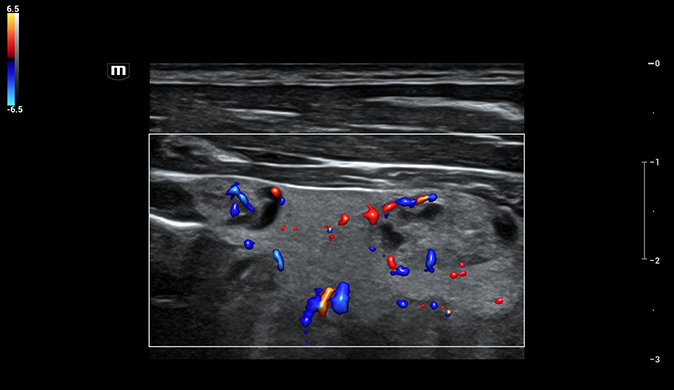

- Glazing Flow: Exibição tridimensional intuitiva de fluxos sanguíneos minúsculos, melhorando diagnósticos vasculares.